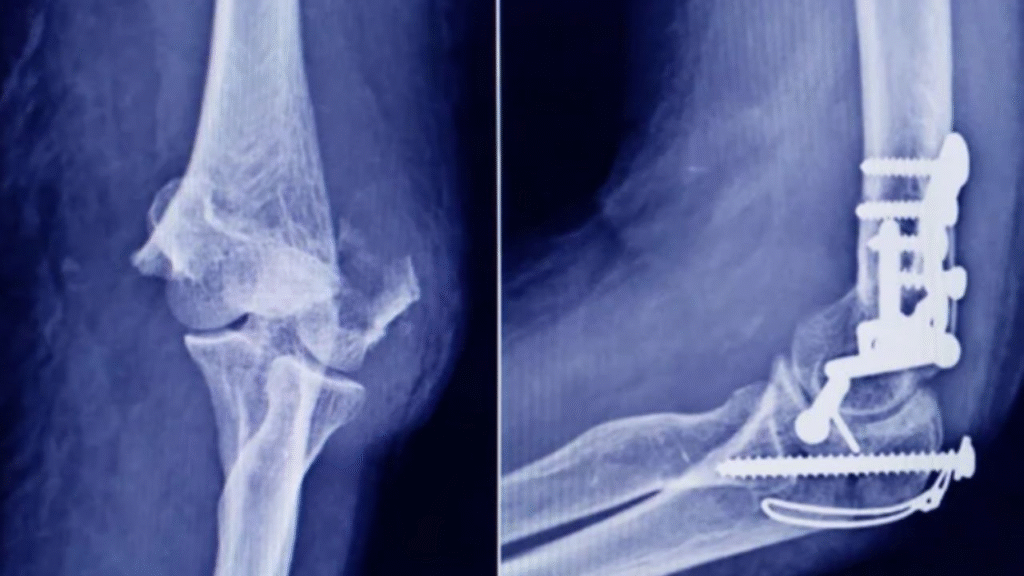

La Administración Nacional de Medicamentos, Alimentos y Tecnología Médica (ANMAT) advirtió a la población por un tornillo utilizado en cirugías traumatológicas debido a que es falso, por lo que su uso representa riesgo para la salud del paciente al que se lo implante.

Se trata de un tornillo utilizado en cirugías traumatológicas que fue detectado durante una inspección de control de mercado realizada en una ortopedia ubicada en la ciudad de San Miguel de Tucumán.

Dicho tornillo es producido por la firma Stryker Corporation, que se encuentra registrada ante ANMAT bajo el PM 594-139. Luego de la inspección, se exhibió la muestra recolectada ante la responsable técnica de dicha empresa, quien afirmó que se trataba de un producto falsificado.

Las autoridades de la ANMAT dieron a conocer las características del producto para su advertencia: STRYKER 10 mm X 28 mm – BIOABSORBABLE – ACL INTERFERENCE SCREW – REF 234-010-067 – LOT 90905.